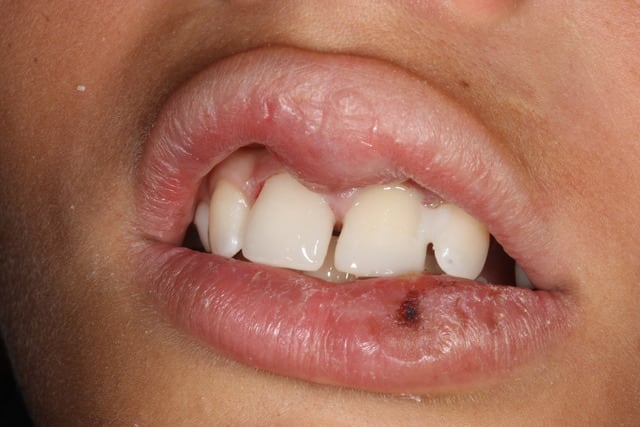

Bon, le gosse était épuisé malgré son courage, j'ai pas pu tout faire, la 21 est très très douloureuse. La 11 va au poil à priori.

J'ai pris l'emp pour faire la gouttière mais je le reverrai demain ou lundi quand il ira mieux pour déposer la contention 21-22 et lui donner la gouttière.

01/08/2014 à 09h55

A wakrap trop bo . on dirait même tes dents !

Tu vois que c est rigolo l extraction réimplantation.

Par contre je n ai pas d expérience aves une mise en charge quasi immédiate. Tu fais plus fort que moi